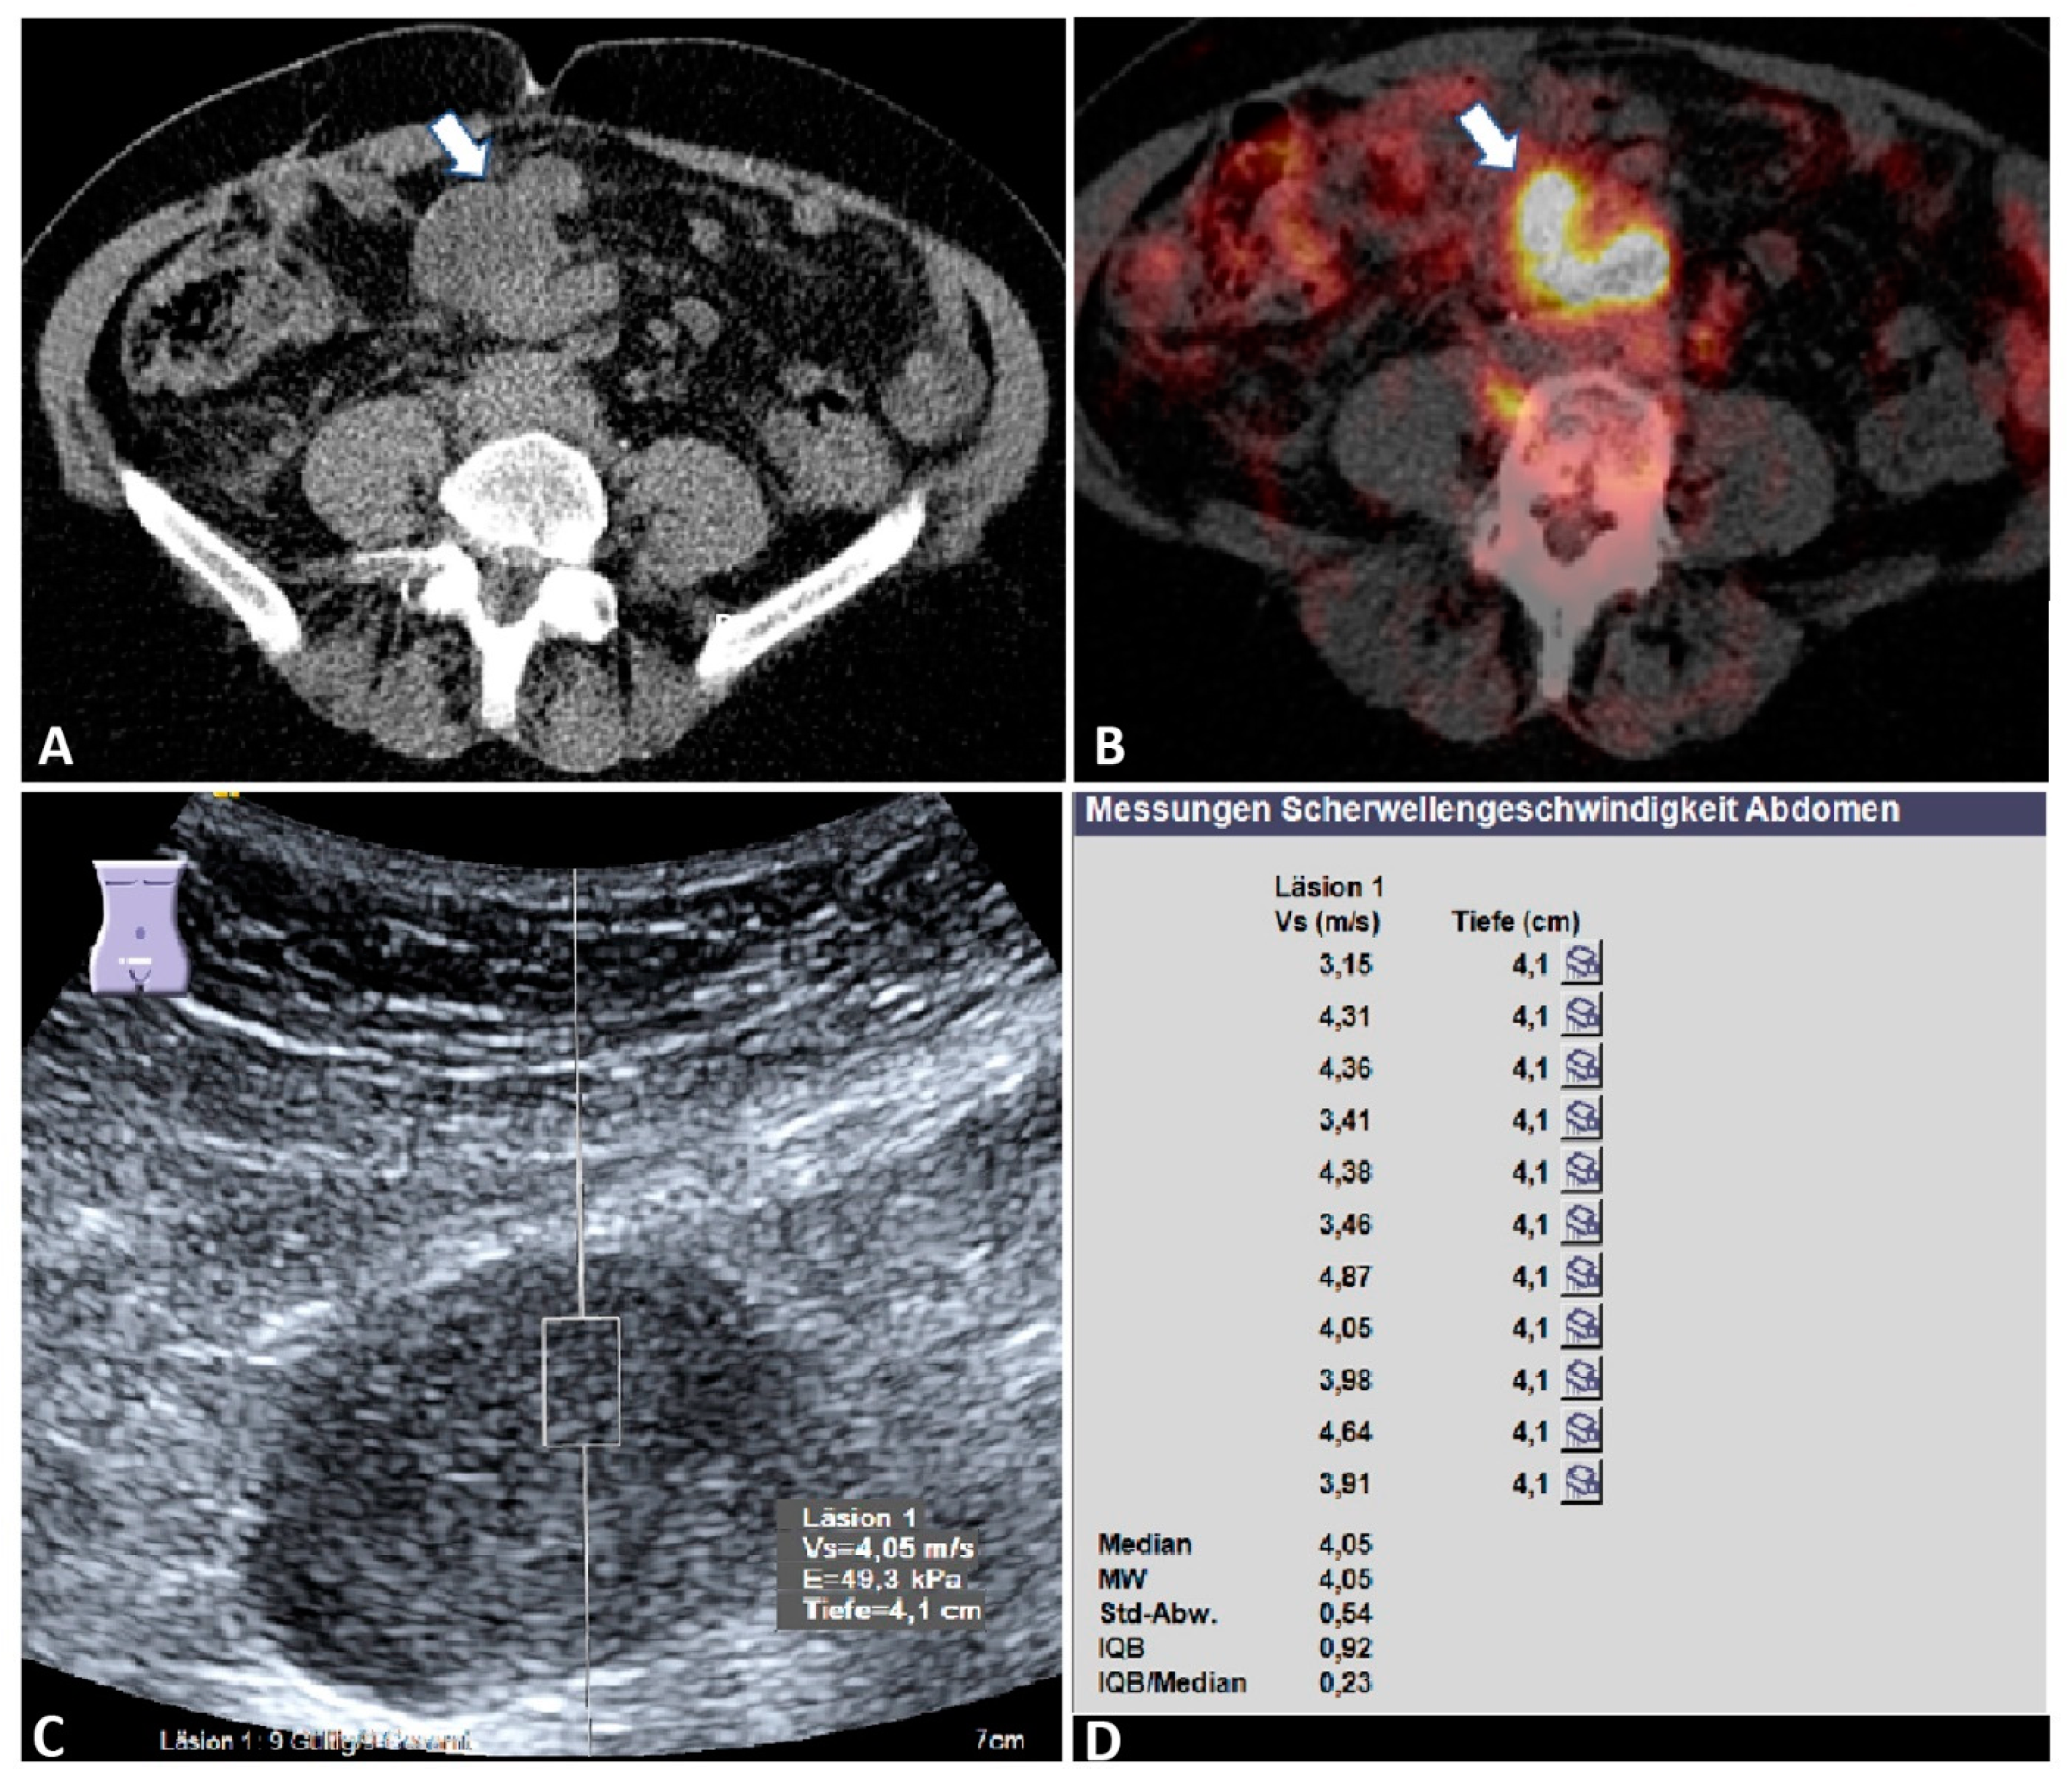

Figure 3.

Malignant mesenteric mass. A 76-year-old female patient with a known history of ovarian cancer and suspected recurrence on staging. (A) Computed tomography image (left) shows a hypointense mesenteric mass (arrow) (courtesy of Prof. Dr. Mahnken, Department of Radiology, University Hospital Marburg); (B) positron emission tomography–computed tomography reveals a high intensity of fluorodeoxyglucose uptake within the mass (arrow)), indicating mesenteric metastasis (courtesy of Prof. Dr. Luster, Department of Nuclear Medicine, University Hospital Marburg); (C) B-mode ultrasound showing a hypoechoic mesenteric mass; (D) the final acoustic radiation force impulse (ARFI) report of the same mass, showing a mean ARFI velocity (MW) of 4.05 m/s. Läsion 1: lesion 1; Vs (m/s): velocity in meter per second; Tiefe (cm): depth in centimeter; MW = mean value (Mittelwert); Std-Abw.: standard deviation (Standard Abweichung); IQB = interquartile range (Interquartilbereich); E: elasticity in Kilopaskal (kPa).